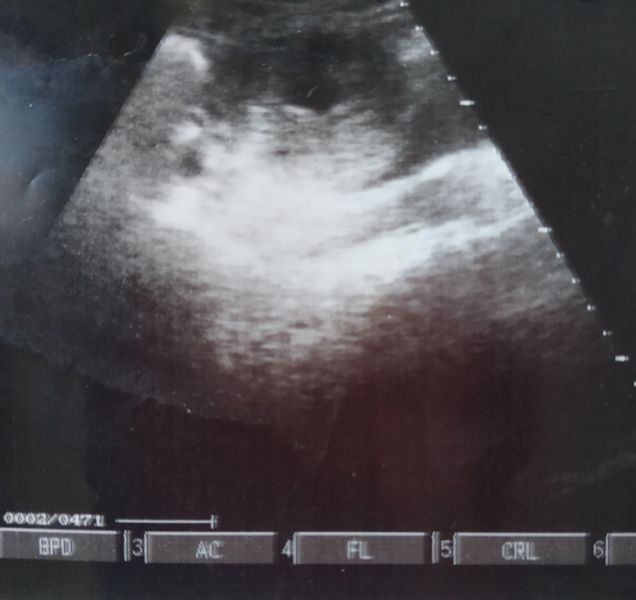

Usg 5 Minggu Belum Terlihat. Tunggu saja dengan bertambahnya usia dan besarnya maka akan semakin terlihat. Janin biasanya baru terlihat pada USG transvaginal antara 3 hingga 5 minggu kehamilan atau pada saat hCG telah mencapai 1500 hingga 2000. Bila kurang dari itu tentu Anda tidakakan melihat apapun di dalam perut Anda. Sebetulnya kalau mau USG saat usia janin 5 minggu apakah sudah bisa terlihat.

Sama bun saya juga gtu 2 hari yg lewat saya usg menurut HPHT usia nya udah 10 minggu tpi janin nya juga belum terlihat dan dr. For more information and source see on this link. Saya telat haid. Kadang hanya bisa terlihat ada suatu gambaran di dalam kantung kehamilan yang menandakan bukan kehamilan kosong. Teknik USG transvaginal dapat lebih memberikan gambaran hasil yang jelas dalam pemeriksaan kehamilan 5 minggu dan hasilnya pasti berbeda dengan hasil usg kehamilan 6 minggu. Penyebab lain bisa juga karena dipengaruhi oleh cara USG.

Tespack positif 2 garis Hamil 5 minggu namun tidak ada gejala mual dan muntah saat USG janin belum terlihat dan keluar flek coklat apakah ini normal. Pemeriksaan USG akan menunjukkan hasil yang lebih jelas saat nantinya sekitar minggu ke-4 sampai minggu ke-12 kehamilan. Teknik USG transvaginal dapat lebih memberikan gambaran hasil yang jelas dalam pemeriksaan kehamilan 5 minggu dan hasilnya pasti berbeda dengan hasil usg kehamilan 6 minggu. Dr Musa ini orangnya baik ramah dan lucu banget beliau bilang saya datang 2 minggu lagi untuk dicek apakah sudah ada janinnya. Agar USG yang dilakukan tidak sia-sia perhatikan 3 hal.

Kadang hanya bisa terlihat ada suatu gambaran di dalam kantung kehamilan yang menandakan bukan kehamilan kosong. Tunggu saja dengan bertambahnya usia dan besarnya maka akan semakin terlihat. Pemeriksaan USG akan menunjukkan hasil yang lebih jelas saat nantinya sekitar minggu ke-4 sampai minggu ke-12 kehamilan. Teknik USG transvaginal dapat lebih memberikan gambaran hasil yang jelas dalam pemeriksaan kehamilan 5 minggu dan hasilnya pasti berbeda dengan hasil usg kehamilan 6 minggu. Nya belum mendengar detak jantung janin nya 1 minggu lagi di suru cek kalau juga belum ada detak jantung nya dokter nya bilang terpksa harus di kuret sedih bgt dengar nya bun ini baru anak pertama.

Jadi hal yang wajar jika janin belum terlihat. Sebab pada usia tersebut sudah bisa dideteksi kantung kehamilan serta perkembangan janin di dalam perut ibu. Nya belum mendengar detak jantung janin nya 1 minggu lagi di suru cek kalau juga belum ada detak jantung nya dokter nya bilang terpksa harus di kuret sedih bgt dengar nya bun ini baru anak pertama. Teknik USG transvaginal dapat lebih memberikan gambaran hasil yang jelas dalam pemeriksaan kehamilan 5 minggu dan hasilnya pasti berbeda dengan hasil usg kehamilan 6 minggu. Pemeriksaan USG akan menunjukkan hasil yang lebih jelas saat nantinya sekitar minggu ke-4 sampai minggu ke-12 kehamilan.